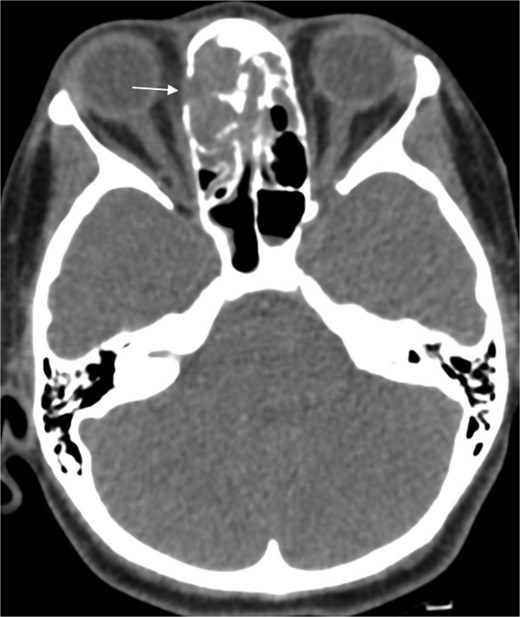

A previously healthy 36-year-old man presented to the emergency department complaining of persistent frontal headache, dizziness, and vomiting of 1 month duration, with no history of orbital complaints (e.g. visual deficits or swelling) or neurological deficits (e.g. limb weakness or seizure-like movements). On examination, the nasal endoscopy showed dry crusts filling the right nasal area. Therefore, due to the subtle symptoms’ origin, the patient was admitted, and a computed tomography (CT) scan of the head and a magnetic resonance imaging (MRI) of the brain were scheduled. The head CT scan revealed complete opacification of the maxillary, ethmoid, frontal, and sphenoid sinuses with bone destruction affecting the left lamina papyracea and roof of the ethmoid air cells (Fig. 1A). The brain MRI demonstrated similar findings with intra-orbital extension resulting in left global proptosis, which triggered concerns regarding fungal rhinosinusitis (Fig. 1B). Accordingly, the patient underwent functional endoscopic sinus surgery (FESS) with a right frontal craniotomy and partial removal of the infected brain tissue on the fourth day of his presentation. Specimens from both surgical sites were sent for pathology and cultures during the surgery. The histopathological results confirmed the diagnosis of CGIFRS, and A. flavus was found in the tissue culture. Postoperatively, the patient was stable, and intravenous antifungal treatment (amphotericin B and voriconazole) and high-dose steroid administration (dexamethasone) were started promptly following confirmation of CGIFRS via pathology. One week after the surgery, the patient’s condition suddenly deteriorated: he had a right fixed dilated pupil and spikes of fever. An urgent brain MRI with contrast was performed, which showed an intracranial abscess, and a significant midline shift to the right side (Fig. 2A and B). The patient, therefore, had a right decompression craniotomy and remained intubated and ventilated in the intensive care unit to receive the maximum medical therapy. However, despite this intensive treatment, the patient’s condition continued to worsen, and he ultimately died after 2 weeks.

(A) Paranasal sinuses CT scan without contrast showing opacification of the sinuses with hyperdense contents. It results dehiscence of the left lamina papyracea and extension in the medial extraconal space (arrowhead). The ethmoid air cells roof show dehiscence of the roof with intracranial extension (arrow). (B) Coronal T2 MRI through the posterior aspect of left orbit shows the intra-orbital extraconal extension as well as the hypointense left ethmoidal disease with extradural intracranial extension.